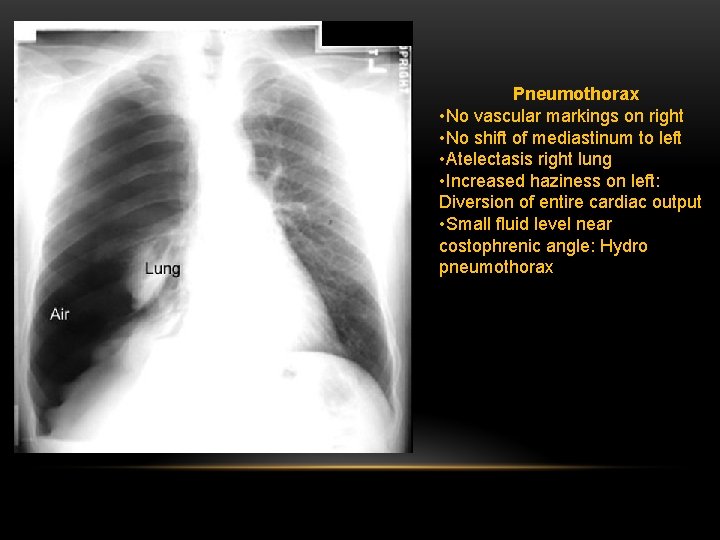

Pneumothorax • No vascular markings on right • No shift of mediastinum to left • Atelectasis right lung • Increased haziness on left: Diversion of entire cardiac output • Small fluid level near costophrenic angle: Hydro pneumothorax